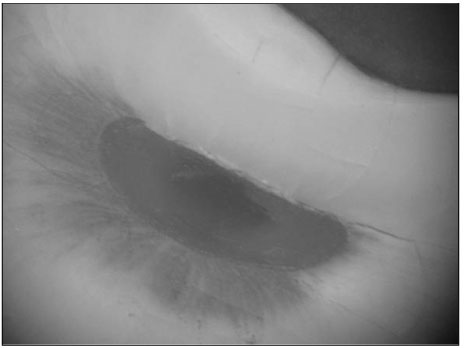

Figure 1

Photograph of the physiologic foramen of distal root (×60)

Figure 2

Photograph of the physiologic foramen of mesial root (×60)